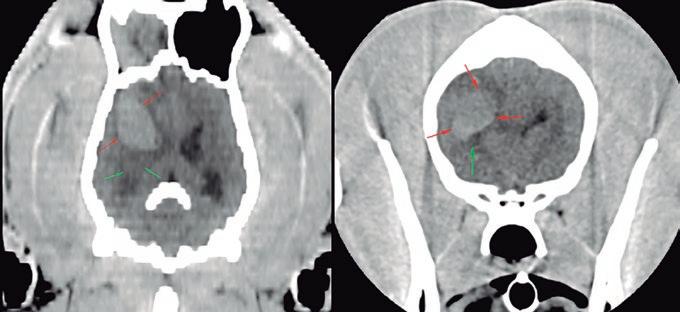

La responsabilidad de los artículos, reportajes, comunicados, etc. recae exclusivamente sobre sus autores. El editor sólo se responsabiliza de sus artículos o editoriales. La ciencia veterinaria está sometida a constantes cambios. Así pues es responsabilidad ineludible del veterinario clínico, basándose en su experiencia profesional, el correcto diagnóstico de los problemas y su tratamiento. Ni el editor, ni los autores asumen responsabilidad alguna por los daños y perjuicios, que pudieran generarse, cualquiera que sea su naturaleza, como consecuencia del uso de los datos e información contenidos en esta revista. De acuerdo con la normativa vigente en materia de protección de datos Grupo Asís Biomedia, SL., es responsable del tratamiento de sus datos personales con la finalidad de enviarle comunicaciones postales de nuestras revistas especializadas, así como otras comunicaciones comerciales o informativas relativas a nuestras actividades, publicaciones y servicios, o de terceros que puedan resultar de su interés en base a su consentimiento. Para ello, Grupo Asís podrá ceder sus datos a terceros proveedores de servicios de mensajería. Podrá revocar su consentimiento, así como ejercer sus derechos de acceso, rectificación, supresión, oposición, limitación y portabilidad enviando un correo electrónico a protecciondatos@grupoasis.com, o una comunicación escrita a Grupo Asís en Centro Empresarial El Trovador, planta 8, oficina I, Plaza Antonio Beltrán Martínez 1, 50002, Zaragoza (España), aportando fotocopia de su DNI o documento identificativo sustitutorio e identificándose como suscriptor de la revista. Asimismo, si considera que sus datos han sido tratados de forma inadecuada,